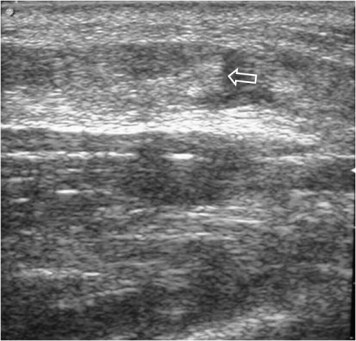

Ambos son signos ecográficos de rotura muscular. En el corte longitudinal al eje muscular, el «badajo» corresponde a la imagen redondeada del extremo retraído del músculo, rodeado de hematoma.

En este esquema está representado un fragmento muscular que sufre una rotura (arriba). Abajo, las fibras afectadas por la rotura se retraen y aparece un hematoma (en rojo) en la zona de la sección de fibras. La “punta” del haz de fibras roto impronta en la zona del hematoma con un aspecto que ha sido definido como signo del badajo de campana (flecha).

Signo ecográfico de rotura muscular en el corte transversal al eje del músculo. El signo corresponde al músculo retraído rodeado de un halo de hematoma.

El Signo del halo también se ve en la rotura muscular pero es un signo visible en el corte transversal al eje del músculo. El signo corresponde al músculo retraído rodeado de un halo de hematoma.

En el mismo esquema anterior, se representa un corte transversal a la altura de la lesión (la línea negra). El signo corresponde al músculo roto y retraído rodeado de hematoma.